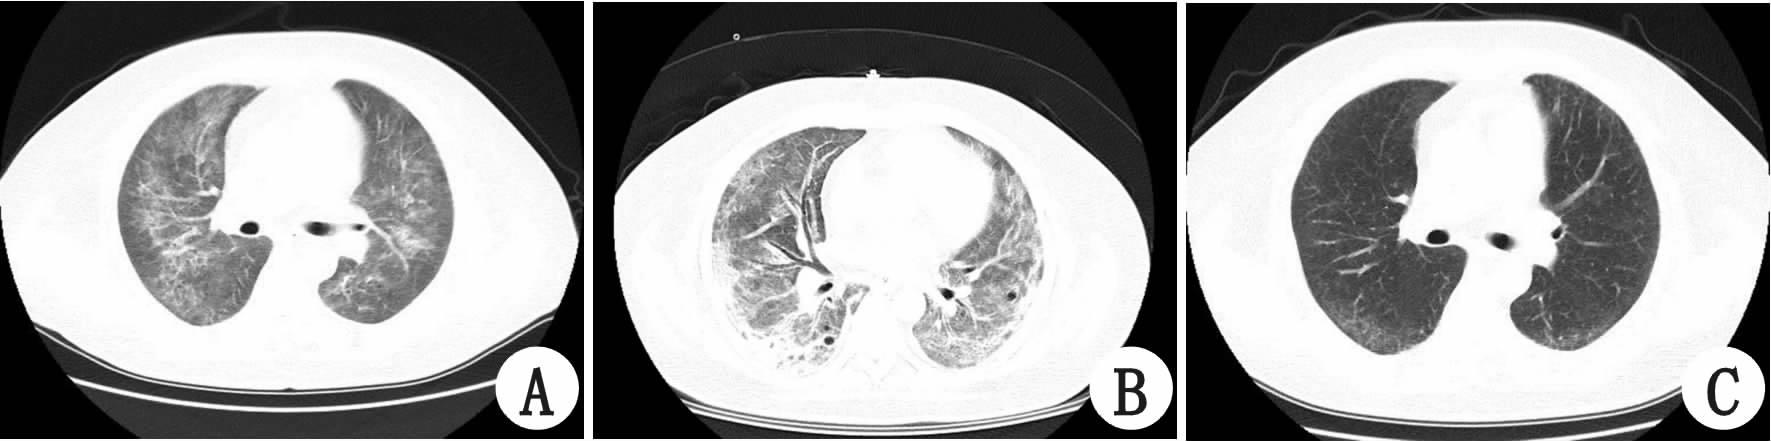

1 资料与方法患者,男性,45岁,既往体健,因“皮肤出血点2个月”于2015年9月22日收入大连医科大学附属第一医院血液科。曾就诊于当地医院,血红蛋白及血小板呈进行性下降,骨穿后诊断为骨髓增生异常综合征-难治性血细胞减少伴多系发育异常,疗效差。间断头痛难忍,双手麻木,发作性言语不清,且神经系统症状进行性加重,出现黄疸。查体:T 36.9 ℃,P 72次/min,R 18次/min,BP 110/70 mmHg(1 mmHg=0.133 kPa);贫血貌,全身散在出血点,巩膜及皮肤黄染;心肺腹及神经系统未见阳性体征。我院头部CT未见异常;血白细胞6.82×109/L,血红蛋白68 g/L,血小板11×109/L;总胆红素39.4 μmol/L;乳酸脱氢酶1 121 U/L;网织红细胞比例16.69%;外周血涂片破碎红细胞>10%;ADAMTS13活性<2.5%(正常值68%~131%);尿蛋白质++,尿潜血阳性;肌酐正常;Coombs试验(-),我院诊断为TTP。因病情恶化,出现神志不清,呼吸困难,2015年9月29日转入急诊ICU行机械通气;右股静脉穿刺成功后予血浆置换,3 000 mL/d,静脉滴注甲强龙160 mg/d。10月3日血小板升至131.4×109/L,血浆置换量减为2 000 mL/d;10月5日血小板骤降至9.4×109/L,穿刺处渗血,右下肢肿胀且大面积淤青,予局部有效压迫止血,血浆置换量再增至3 000 mL/d,出血倾向好转,10月6日神志转清,10月8日撤呼吸机。然而,在此期间血小板仍低 ,遂将血浆置换量增至3 500 mL/d,并加用利妥昔单抗600 mg/次,每周一次,10月16日血小板升至101×109/L,未再下降,血浆置换量渐减至2 000 mL/d。10月28日复查ADAMTS13活性64%,11月1日出院。共行血浆置换27次,总量达74 500 mL。出院后继续口服泼尼松片,定期复查血小板均正常。该患者12月11日起出现发热,体温39 ℃,咳嗽、少痰,入住外院查血常规正常,PCT 0.134 ng/mL,给予头孢唑林静脉滴注,12月16日肺部CT(图 1A)提示双肺弥漫毛玻璃样斑片影,考虑真菌性肺炎可能,换用卡泊芬净联合莫西沙星后疗效较差,出现喘憋,SPO2降至65%。12月18日转入我科行机械通气,复查肺CT(图 1B)示双肺弥漫性毛玻璃密度影,双肺间质纤维化或间质性肺炎,较前加重;痰真菌培养回报为阴性,细菌培养为正常咽喉菌群生长;G实验291.3 pg/mL,GM实验阴性。经呼吸内科会诊考虑为肺孢子菌肺炎,继续用卡泊芬净联合莫西沙星,加复方磺胺甲噁唑口服,症状渐好转,成功撤呼吸机出院。继续口服复方磺胺甲噁唑,1月22日复查CT见图 1C病灶基本吸收。

| A:12月16日;B:12月18日;C:1月22日复查 图 1 患者CT结果 |

PCP是一个机会感染性疾病,多见于免疫功能缺陷或长期接受免疫抑制剂治疗者,若缺乏针对性治疗,病情迅速恶化,预后极差[4]。其确诊常以肺组织或下呼吸道分泌物发现肺孢子菌包囊和滋养体为金标准;痰阳性检出率低,支气管肺泡灌洗液和支气管肺活检的敏感率可高达90%~95%[4]。本例后期出现重症肺炎,虽未行确诊性检查,但根据病史、临床症状及CT,临床诊断为PCP,予卡泊芬净联合复方甲噁唑诊断性治疗[5]后效果显著。故TTP患者若临床上怀疑PCP,应及时经验性诊断性治疗,切勿贻误治疗时机。